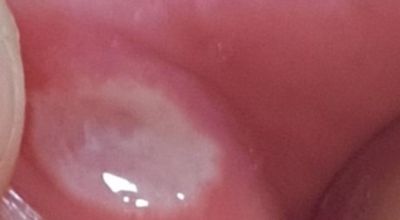

구내염 원인 - 아프타성 구내염

입안 점막이 동그랗게 패여 통증을 유발한다면, 아프타성 구내염을 의심할 수 있어요. 음식을 먹을 때마다 아픈 작은 궤양이 생겼다면, 아프타성 구내염을 의심할 수 있어요. 아프타성 구내염은 빨간색 둘레를 가진 둥근 형태의 흰색 궤양이, 얕은 깊이로 한 개 및 여러 개 생기며 통증을 동반하는 것이 특징입니다. 전 인구의 20~40%가 발병할만큼 통상적으로 나타나는 질환으로 20대, 주로 여성분들에게 많이 나타나며, 일주일 정도면 자연적으로 치유되지만 1~3개월 간격으로 빈번히 재발하는 것이 특징입니다.

까닭은 입 속 점막의 작은 상처나, 바이러스, 세균의 감염, 각별히 수면 부족이나 과로, 스트레스가 축적돼 면역력이 떨어졌을 때와, 비타민 B12 또는 엽산 결핍 시에 많이 생기 다고 알려져 있어요. 흔한 질환이니만큼 자연적으로 치유 되지만, 통증을 동반하고, 궤양의 크기가 커지거나 숫자가 늘어나기도 하기 때문에 연고나 외용제, 가글액 등을 활용해서 증상을 경감시키는 치료를 하기도 해요.